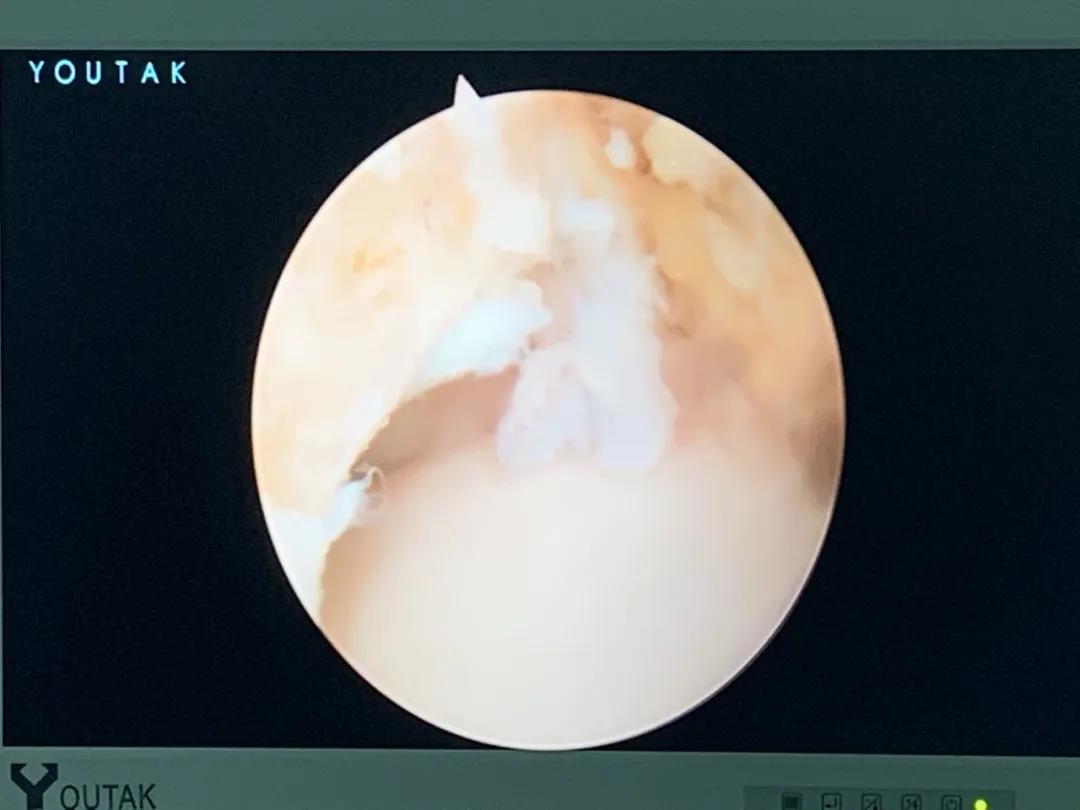

膝關(guān)節(jié)鏡

膝關(guān)節(jié)半月板損傷和前后交叉韌帶損傷是運(yùn)動損傷常見疾病,半月板損傷后不能自行愈合,盡早手術(shù)可以避免繼發(fā)關(guān)節(jié)軟骨的損傷,骨二科采用關(guān)節(jié)鏡下半月板縫合手術(shù),能少切除就少切除,能縫合盡量縫合,最大努力保留患者半月板,更好的恢復(fù)膝關(guān)節(jié)的功能。膝關(guān)節(jié)前后交叉韌帶損傷一般采用單束重建,只能恢復(fù)原來韌帶的80%的強(qiáng)度,骨二科采用雙束重建,能夠比原來的韌帶更粗更強(qiáng),為后期的功能鍛煉及恢復(fù)提供良好的基礎(chǔ)。

關(guān)節(jié)鏡下半月板縫合手術(shù)

關(guān)節(jié)鏡下雙束重建